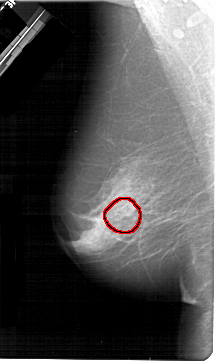

A_1378_1.LEFT_MLO

LEFT_MLO LINES 5431 PIXELS_PER_LINE 3241 BITS_PER_PIXEL 12 RESOLUTION 43.5 OVERLAY

FILE: A_1378_1.LEFT_MLO.OVERLAY

TOTAL_ABNORMALITIES 1

ABNORMALITY 1

LESION_TYPE CALCIFICATION TYPE PLEOMORPHIC DISTRIBUTION CLUSTERED

ASSESSMENT 4

SUBTLETY 4

PATHOLOGY BENIGN

TOTAL_OUTLINES 1

BOUNDARY